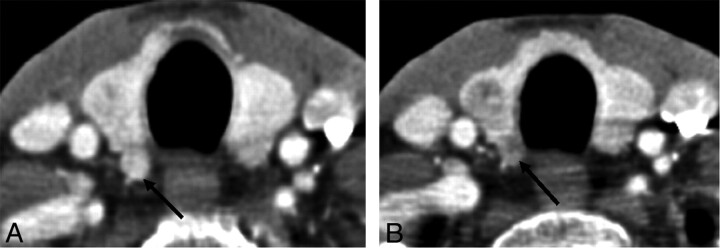

Although the ZT is composed of normal thyroid tissue, nodules may develop within the ZT just as in other normal thyroid tissue (Fig 9). The ZT is commonly left unresected if not involved by tumor to avoid harming the adjacent recurrent laryngeal nerve, and so it can be a future site for recurrence (Fig 10). Recognition of this aspect of thyroid anatomy can help avoid mistaking normal thyroid landmarks as nodules or lymph nodes.

Fig 9.

A, Thyroid gland with a nodular ZT at the posterior aspect of the right lobe (arrow). B, Follow-up CT study demonstrating development of a discrete hypoattenuated nodule in the right lobe and a hypoattenuated nodule in the previously identified ZT (arrow).

Fig 10.

A and B, CT images on a patient status post total thyroidectomy for thyroid cancer show a small enhancing lesion near the right tracheoesophageal groove (arrows), which likely represents a tubercle of Zuckerhandl. C and E, Axial and coronal CT demonstrates enlargement of a paratracheal lesion after an interval of 6 months (arrows in C and E); a nearby lymph node also showed enlargement (arrow in D) and proved to be recurrent disease.